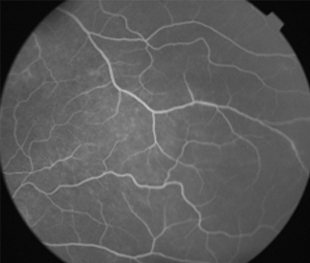

Angiografía OD